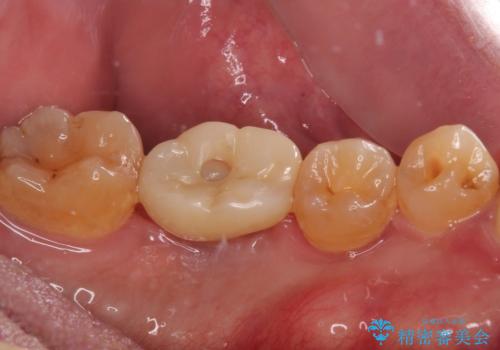

- 食事中に奥歯が痛むとのことで来院された患者様です。

レントゲンやCTより、深くまで破折していることが分かり、抜歯が必要な状態でした。

歯槽骨の状態は良好であったため、抜歯即時埋入インプラントによる補綴治療を行うこととしました。